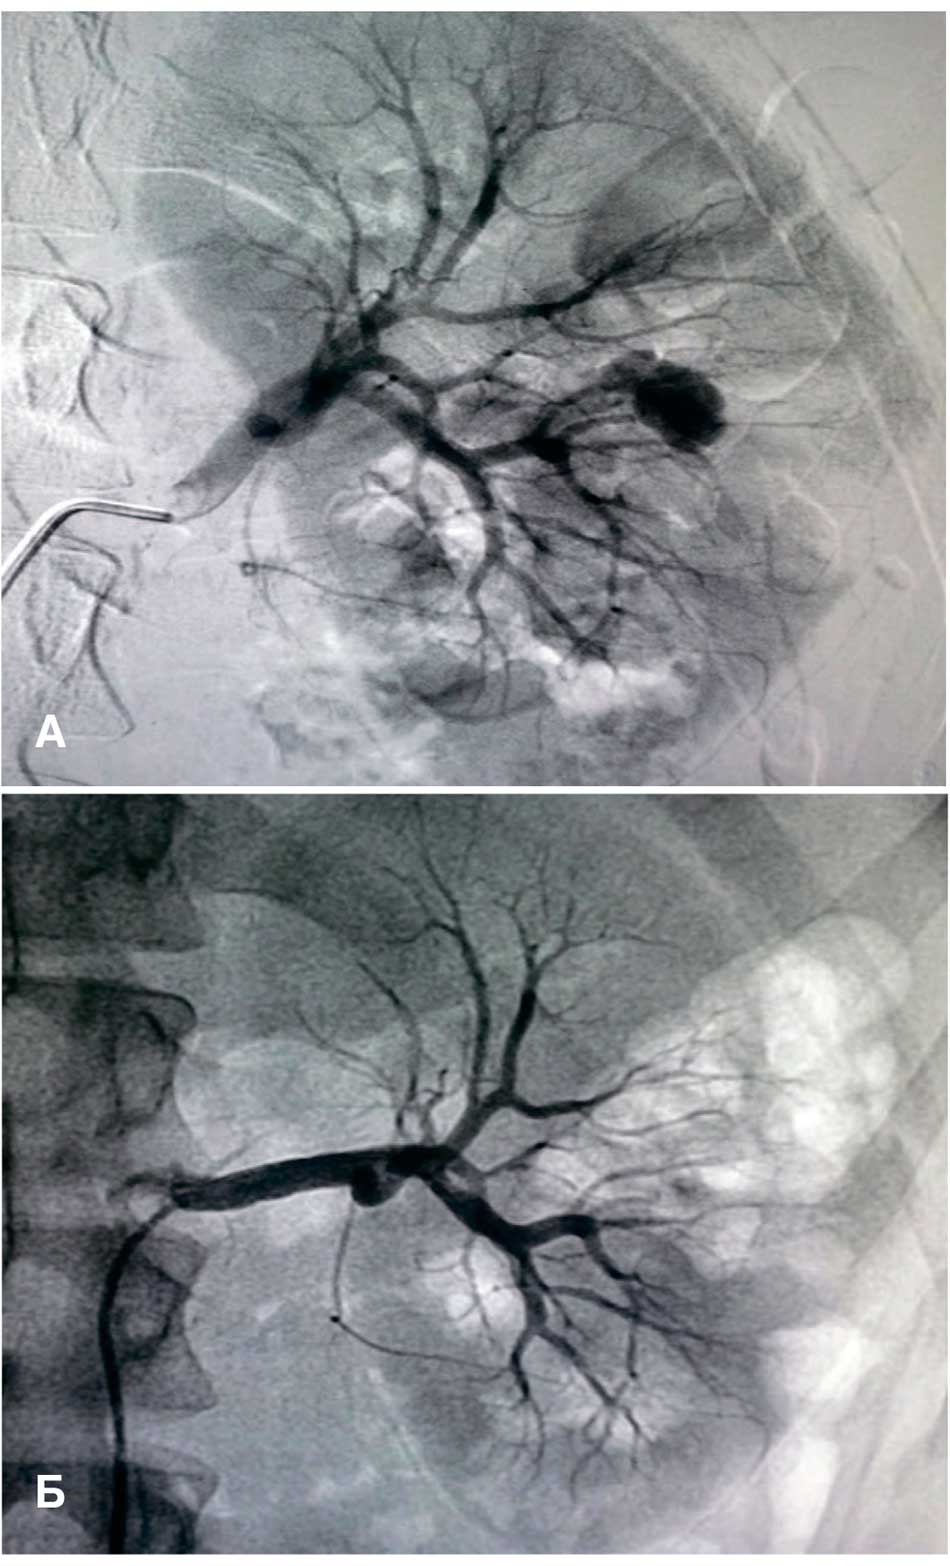

Лечение колото-резаных ранений почки осуществлялось 46 (73%) пострадавшим оперативным и 17 (27%) пациентам консервативным способами. При хирургическом вмешательстве 40 (63,5%) пострадавшим с сочетанными ранениями почки выполнялась лапаротомия. Пятерым пострадавшим с изолированным ранением почки, у которых рана локализовалась со стороны спины, проводилась люмботомия. В одном случае при изолированном ранении почки III степени по шкале AAST с продолжающимся кровотечением гемостаз был достигнут рентгенэндоваскулярным способом (рис. 4).

Рис. 4. Селекивная эмболизация почки: а – экстравазация контрастного вещества из сегментарной почечной артерии до эмболизации; б – после эмболизации сегментарной почечной артерии

Fig. 4. Selective renal artery embolization: (a) renal angiography shows the contrast extravasation from the segmental renal artery before embolization; (b) postembolization renal angiography confirms the disappearance of the extravasation